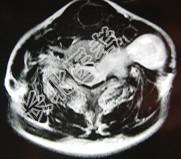

- 单项选择题52岁女性患者,左颈部无痛性包块渐进性增大, MRI检查如图,应需要考虑为 ( )

A、左侧颈部脂肪瘤

B、左侧颈部转移瘤

C、左侧颈部神经纤维瘤

D、左侧颈部神经鞘瘤

E、左侧颈部动脉瘤